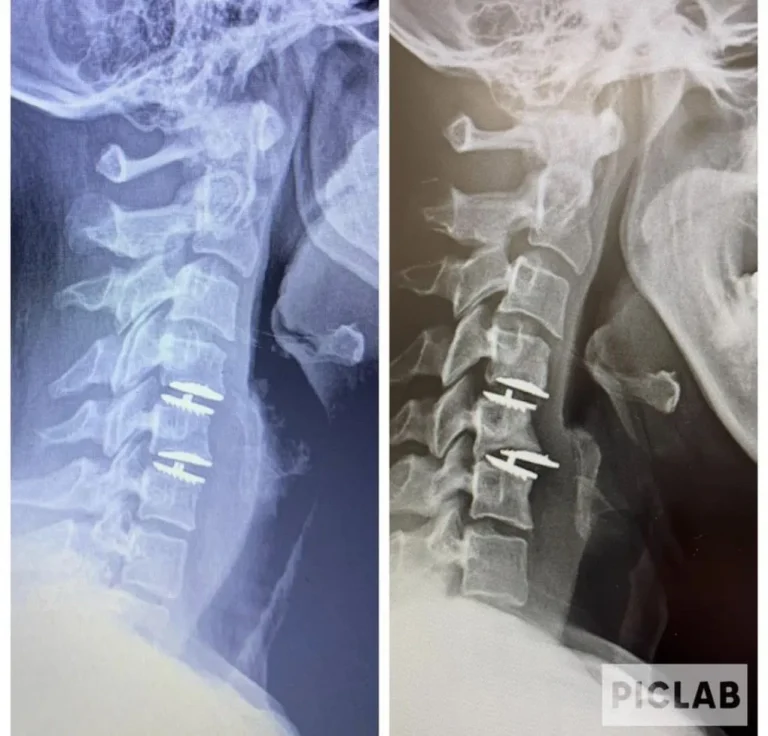

Side-by-side cervical spine X-rays with surgical screws visible.

Artificial Disc Replacement

What Patients Need to Know Before Surgery

Unnecessarily dangerous procedure that benefits the surgeon and device manufacturer more than the patient.